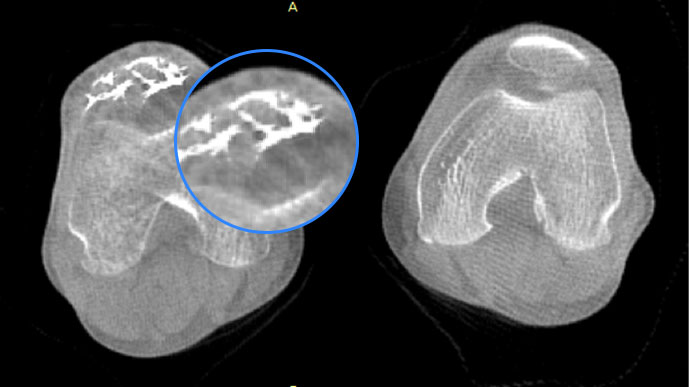

独特的负重位三维影像

填补常规CT/MR空白

助力术前规划和术后评估

• 膝关节